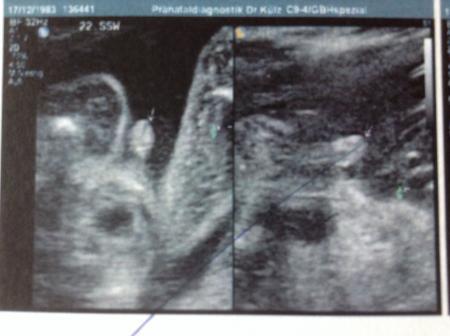

Antwort auf Beitrag von liebe1415

Huhu, Bei uns hieß es erst Mädchen (lag aber auch doof bei dem 2. Screening in der 21. SSW). Bei der Feindiagnostik in der 22. SSW war es dann ein Junge. Anbei das Beweisfoto. Ich gehe mal davon aus, dass es jetzt dabei bleibt ;-).

Bild zu